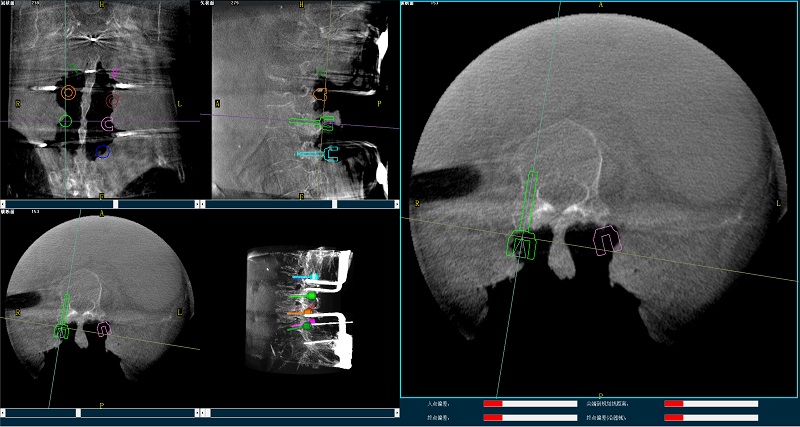

机器人辅助腰椎后路侧弯矫形手术三维图像

三维图像

(2)使用华体会体育登入首页平板三维C形臂扫描患者,得到术中三维图像并传送至骨科机器人导航系统。骨科机器人导航系统基于高清术中三维图像进行手术规划。

机器人辅助腰椎后路侧弯矫形手术规划图像

手术规划图像